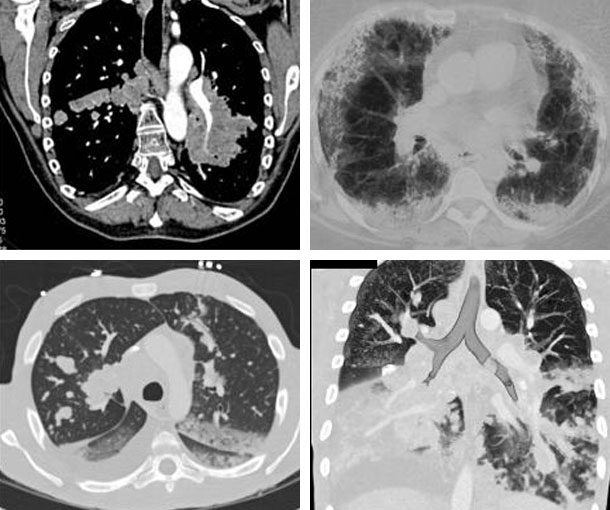

Chest CT Appearances

Pulmonary Lymphoma CT Findings

- Pulmonary consolidation with dilated air bronchograms

- Solid or semisolid pulmonary nodule(s)

- Peribronchovascular interstitial thickening

- Can be unilateral or bilateral

- May have ground-glass attenuation with “halo” sign